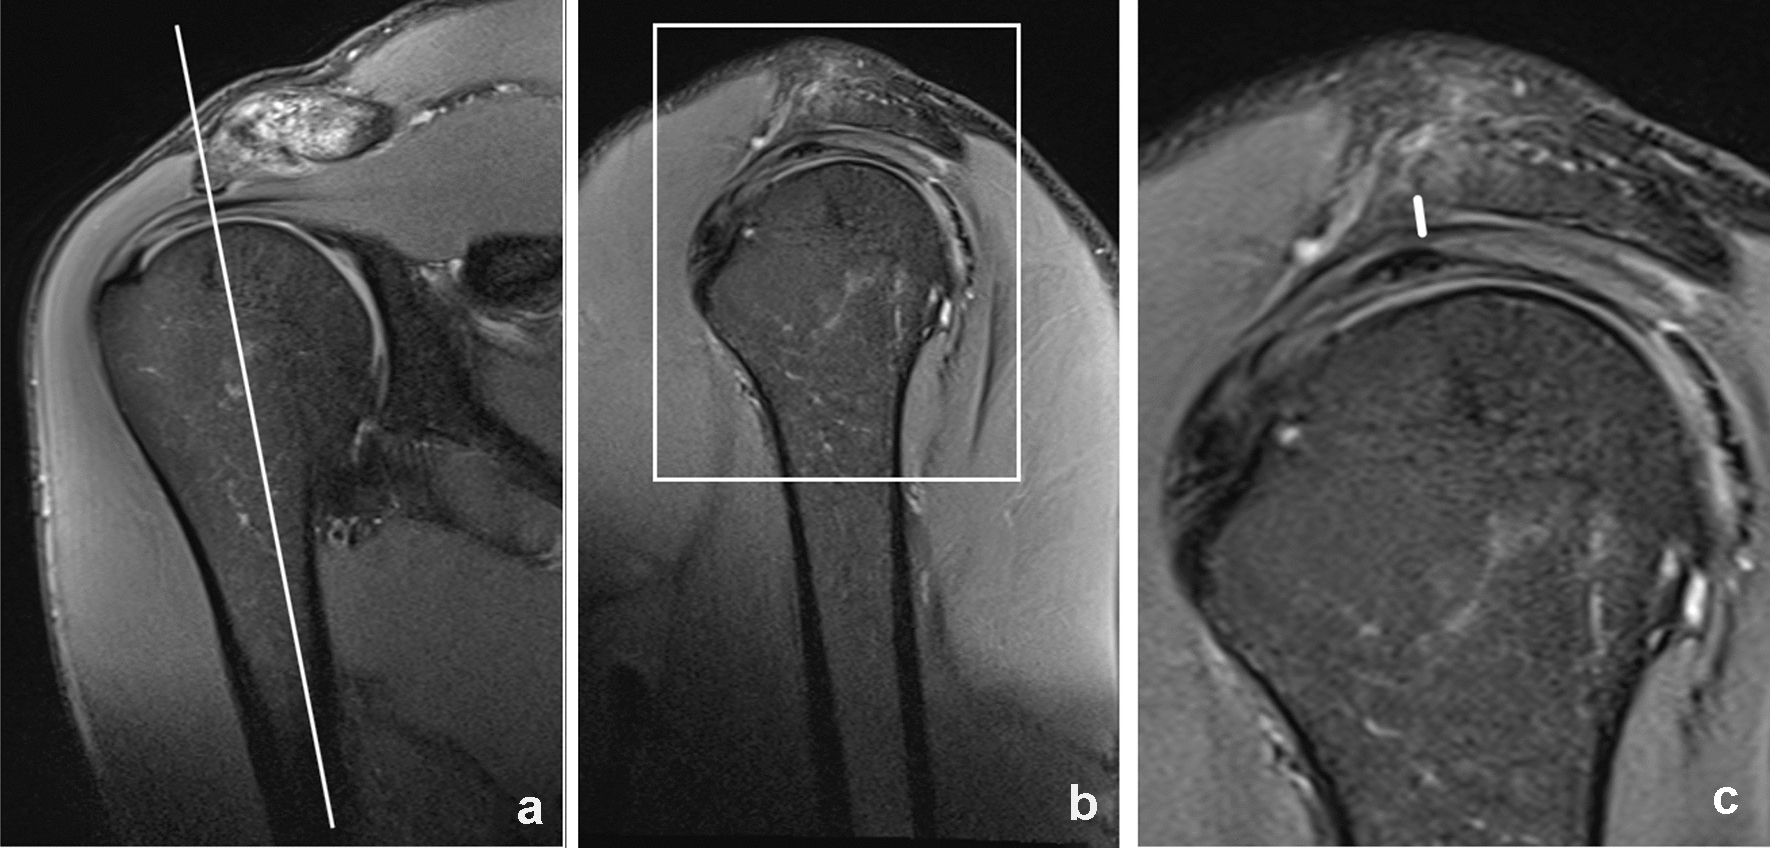

If a subacromial osteophytic spur was present, it was measured in a sagittal plane (see Fig. 3) and the minimal distance between the caudal border of the spur instead of the caudal margin of the acromion itself was referred to when measuring distance to the humeral head (see Fig. 4).

Fig. 3

Measurement of a subacromial spur. Proton-density weighted fat saturated images in a coronal a and sagittal b, c plane. The size of the subacromial spur was measured in a sagittal plane according to the axis of the humeral head, the measured length is represented by a white line in c. The rectangle in b represents the area which is enlarged in c. The white line in a shows the imaging plane of the sagittal images b, c

Fig. 4

Measurement of the subacromial distance. Proton-density weighted fat saturated images in a coronal a and sagittal b plane. The minimum distance between the acromion and the head of the humerus was measured in both planes. In this case the subacromial space was narrowed by a subacromial spur